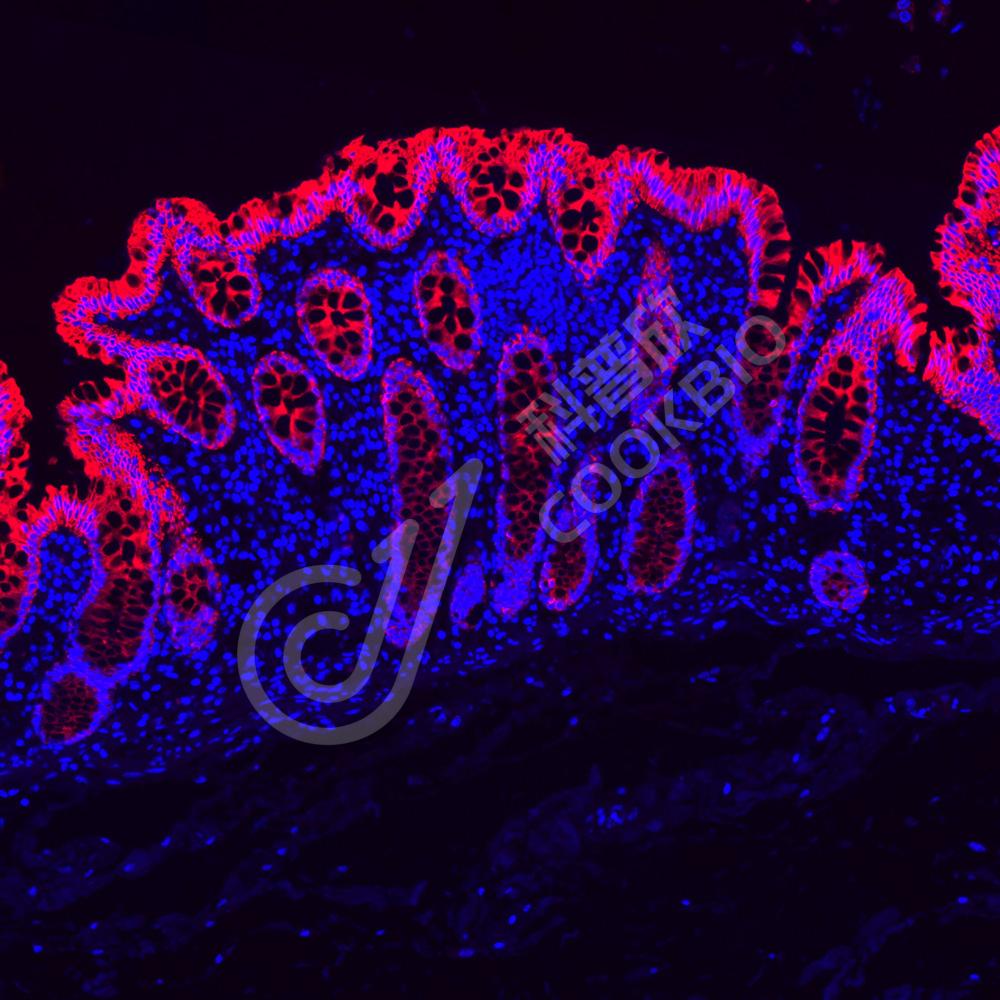

IF检测Cytokeratin 8蛋白(货号 K133693)(红色).

样品: 人结肠, 4%多聚甲醛 (货号KSG1101) 固定12-24小时.

抗原修复: Tris-EDTA抗原修复液(pH 9.0) (KSG1203), 98℃, 20分钟.

封闭: 3% BSA(货号KSGC305010)的PBS溶液, 室温孵育30分钟.

—抗: 1: 600稀释, 4℃ 孵育过夜.

二抗: Cy3标记山羊抗兔IgG (H+L) (货号KB63909), 1: 300稀释, 室温孵育1小时.